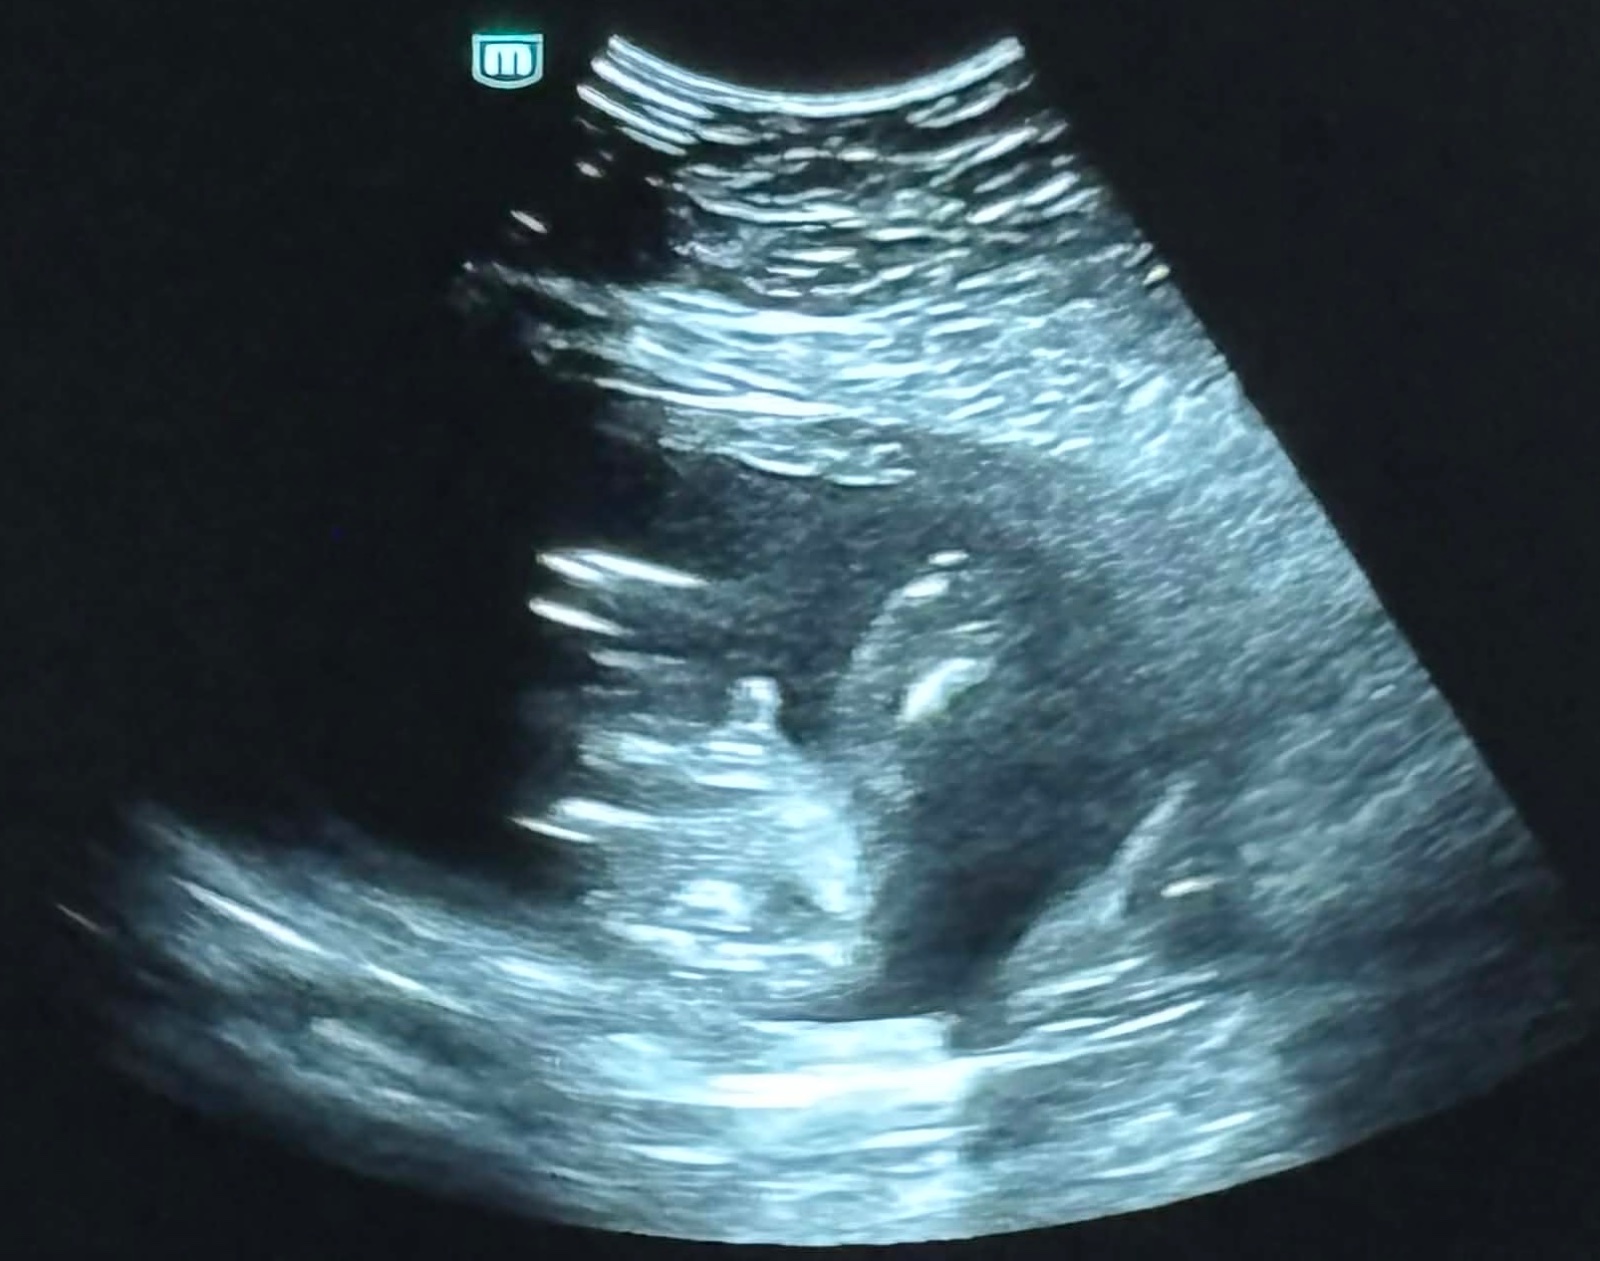

Sono v 20. týždni tehotenstva - pohlavie bábätka

Môj gynekológ po opakovanej snahe nevie s istotou povedať pohlavie dieťaťa. Tvrdí, že test z krvi je zbytočný a stále hovorí, že nabudúce sa dozvieme čo to je, no nevychádza nám to. Bábätko sa veľmi hýbe. Je zdravé a vyvíja sa v poriadku- to je to najdôležitejšie.

(Pán doktor nevidí miešok, no niečo tam zahliadol a podľa môjho osobného názoru to môže byť aj pupočník)

Nie, nechcela by som aby moje dieťa bolo hermafrodit a videla som tú foto, ano. Pre mňa to vyzerá ako pupočník. Fotka je fotená odspodu a má tam zachytené stehienka.